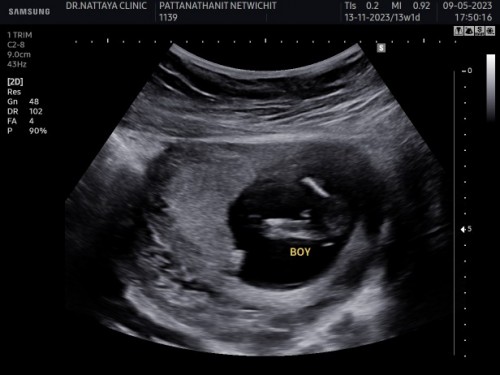

หมอบอกว่าน้องเป็นผู้ชาย

13w1dหมอบอกว่าน้องเป็นผู้ชาย แม่บ้านนี้อยากได้ลูกชายมาก จากภาพอัลตร้าซาวด์แม่ๆฟันธงได้ไหมค่ะว่าน้องเป็นผู้ชาย

มียื่นๆ ออกมา ก็น่าจะชายนะคะ😁